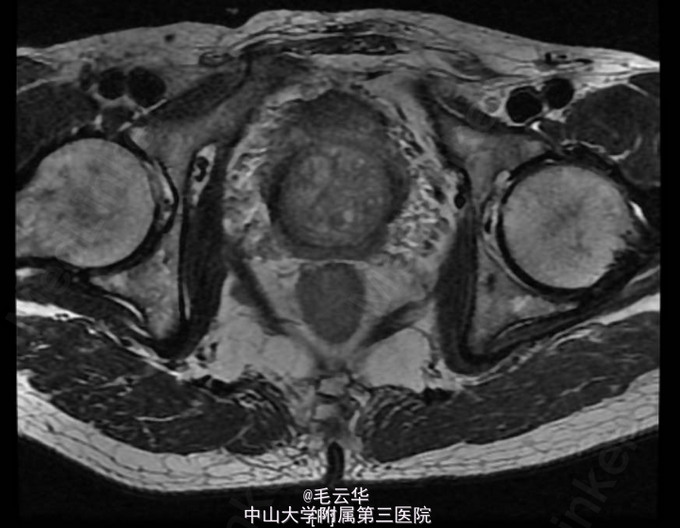

入院诊断:急性尿潴留,前列腺增生症 鉴别诊断:1.前列腺癌 2.膀胱颈纤维化 3尿道狭窄 4 神经源性膀胱 入院完善相关检查,盆腔MR示前列腺增生;左侧外周带T2WI信号降低,恶变待排,建议活检。B超引导下证实前列腺癌Gleason3+3=6分。行腹腔镜下前列腺癌根治术。术后病理示前列腺腺癌(Gleason评分:3+3=6分),闭孔淋巴结未见癌。